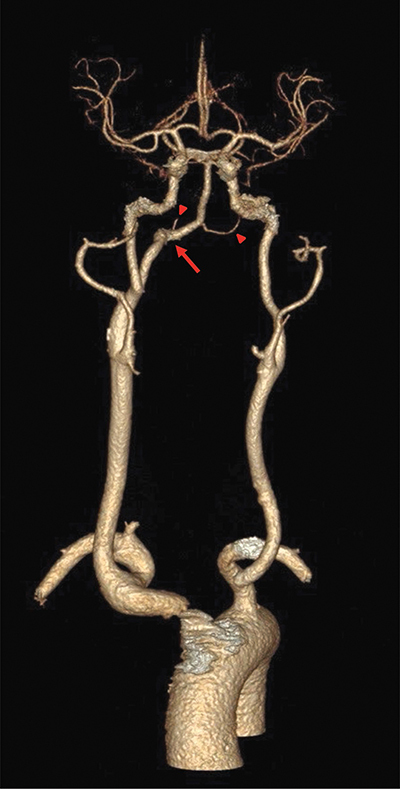

教学要点:持续性舌下动脉是一种极其罕见的解剖变异,但具有诊断和治疗意义。

Teaching point: Persistent hypoglossal artery is an extremely rare anatomical variant but has diagnostic and therapeutic relevance.